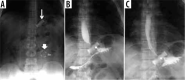

Material and methods: We retrospectively review 954 obese patients who underwent bariatric surgery between 2013 and 2019. The study included 72 patients who developed clinical suspicion of acute complications (painful and meteoric abdomen, nausea, vomiting, fever, intestinal blockage) within 6 days of bariatric surgery of sleeve gastrectomy, gastric banding, gastric bypass with Roux loop confirmed by CT, and who underwent a gastrointestinal transit before the CT examination.

Results: GI exam allowed visualisation of 58% of complications. Analysing the data for each surgical technique, 46 post-operative complications were found involve gastric banding. The most frequent was bandage migration (26 cases, 56 %), identified in all cases at GI transit and then confirmed on CT.